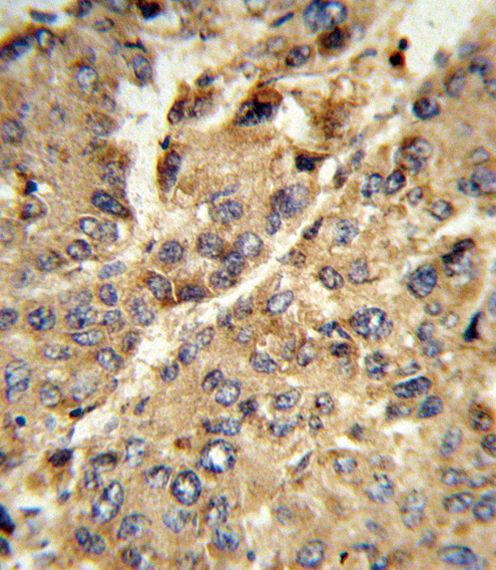

IHC-P analysis of human hepatocarcinoma using GTX80444 Xanthine Oxidase antibody, N-term.